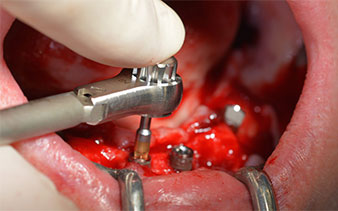

After removal of the residual dentition in the mandible, the alveolar crest was exposed from 37 to 47.

The mental foramen was first identified as a limiting anatomical structure and then the cortical bone of the crest was smoothed with the straight handpiece and a large rose-head bur (Fig. 4).

The surgical protocol for the implants employed (SKY, bredent medical) specifies a speed of 1,200 rpm for the pilot drilling (Fig. 7 - 9).

This corresponds to the next preset position in the Implantmed. Here we see the W&H contra-angle handpiece being held at a 45° angle to mesiocaudal in the region of 45 in order to preserve the mental nerve. The mental foramen is used as the anatomic reference for all drilling in this region. The subsequent holes were drilled at a reduced speed of 300 rpm (Fig. 10 and 11).